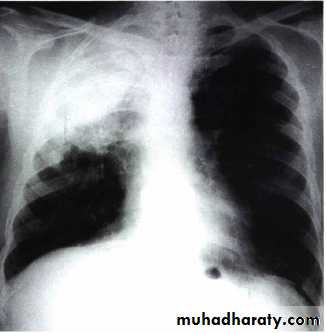

A 55 years-old smoker man presented with cough, hemoptysis, unilateral chest pain and dyspnea for 3 months.

Later on, fever, greenish sputum, and increasing dyspnea developed.

He felt unwell and his appetite was decreased.

General examination showed finger clubbing.Chest examination revealed decreased chest expansion, dull percussion and bronchial breathing on auscultation on one side.

LUNG CANCER - Dr. Mustafa Nema- Baghdad College of MedicineChest-X Ray showed an abnormal lung shadow and pneumonia-like lesion.

Antibiotic given but, pneumonia didn’t resolve completely.• How can you manage

this patient?